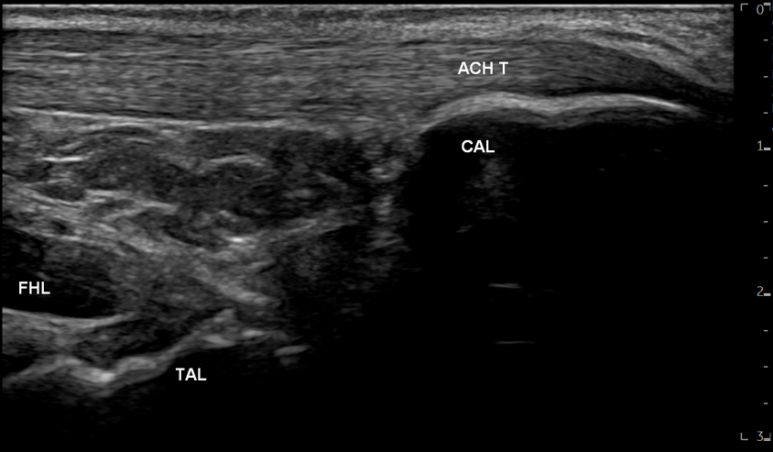

영상에서

족태양경근은 깊이에 따라

아킬레스건, 장무지굴근, 종골, 거골 등

다양한 구조물이 보입니다.

그 중에

아킬레스건(ACH T)은흰색 줄무늬 섬유 패턴으로보이는데요.

위 환자분은

아킬레스건이

많이 부어있으셨고요.